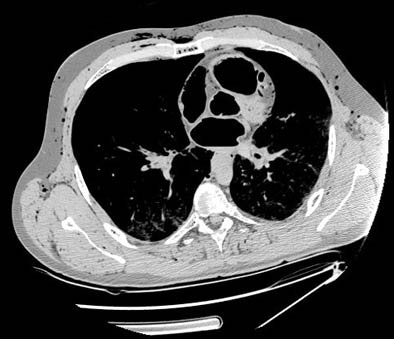

| Axial MDCT scan revealing massive air embolism in the heart cavities as well as air in the soft tissues in a fatal diving incident. Image courtesy of Dr. Michael Thali. |